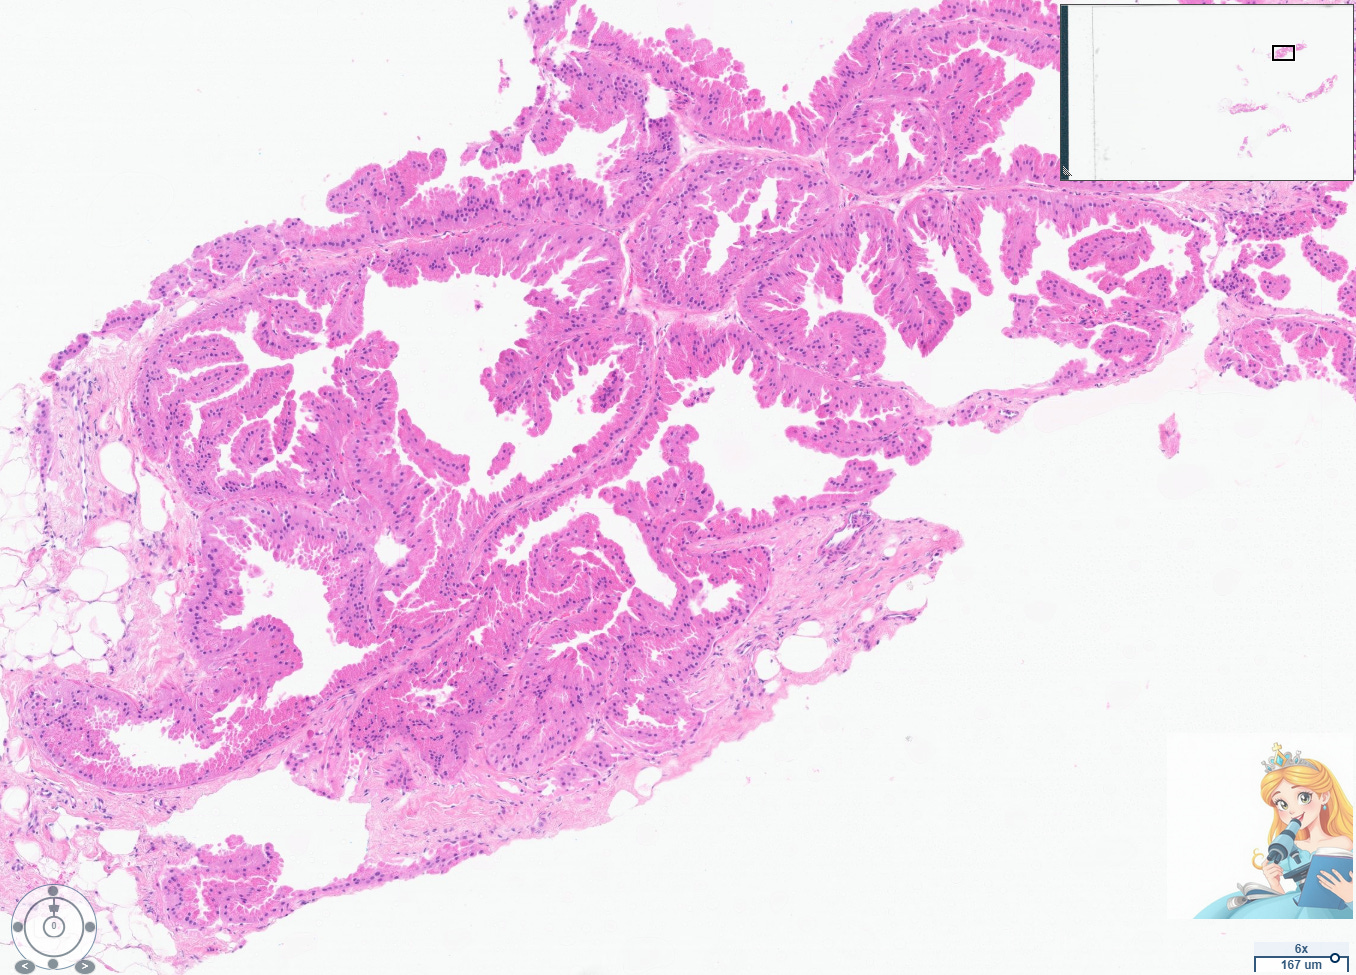

Apocrine cysts are a common manifestation of fibrocystic change in the breast, particularly in women over 25 years old. These cysts are lined by apocrine cells, which are characterized by abundant eosinophilic granular cytoplasm, round nuclei with pale chromatin, and prominent nucleoli. The apocrine lining may be cuboidal or columnar, and the cells typically have a low nuclear-to-cytoplasmic ratio and prominent apical snouts, reflecting apocrine secretion.[1-2]

Abundant apocrine cystic change has been termed cystic papillary apocrine metaplasia by pathologists. However, using this term diagnostically can be confusing to radiologists who are concerned that the term “papillary” warrants consideration for excision. Always rule out a papilloma with apocrine changes when evaluating this particular type of apocrine changes, which can appear architecturally complex.